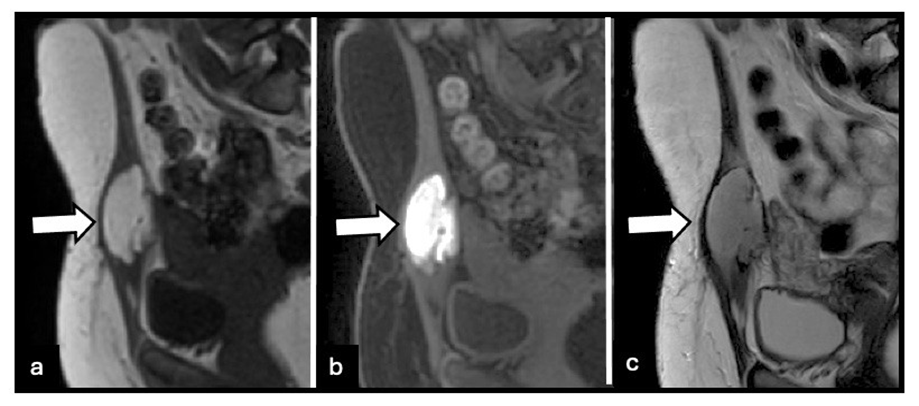

MRI is the reference standard for evaluating abdominal wall and intramuscular endometriosis. Imaging features vary according to lesion composition. Predominantly fibrous lesions exhibit low to intermediate signal intensity on T2-weighted images, often with ill-defined margins and infiltrative growth patterns (Figure 1). Intramuscular cystic lesions may be well-circumscribed, occasionally resembling ectopic ovarian endometriomas (Figure 2). Infiltrative intramuscular lesions with hemorrhagic microcysts present as punctate or confluent hyperintense foci on fatsuppressed T1-weighted images (Figure 3). Overall, lesions can be iso- to hyperintense relative to muscle on T2-weighted images, with focal T1 hyperintensity reflecting hemorrhagic components, a feature highly suggestive of endometriosis. [3,5] After gadolinium administration, lesions usually demonstrate moderate to marked, often heterogeneous, enhancement. Lesions may appear nodular, spiculated, or retractile and can infiltrate adjacent muscular layers, including the rectus abdominis or oblique muscles. Diffusionweighted imaging often demonstrates intermediate diffusion restriction, with reported apparent diffusion coefficient (ADC) values around 0.93 × 10⁻³ mm²/s. [5] MRI also permits accurate delineation of lesion extent through the abdominal wall layers and facilitates detection of concurrent pelvic disease, which is essential for comprehensive surgical planning [3,5].

Figure 2: 25-year-old woman with intramuscular cystic abdominal wall endometriosis involving the left rectus abdominis muscle. (a) Sagittal T1-weighted MRI image shows a well-circumscribed predominantly cystic lesion with high signal intensity (arrow). (b) Fatsuppressed T1-weighted MRI image demonstrates marked hyperintensity, consistent with hemorrhagic content (arrow). (c) Sagittal T2weighted MRI image shows heterogeneous signal intensity with a well-defined fluid component (arrow), resembling an ectopic ovarian endometrioma.